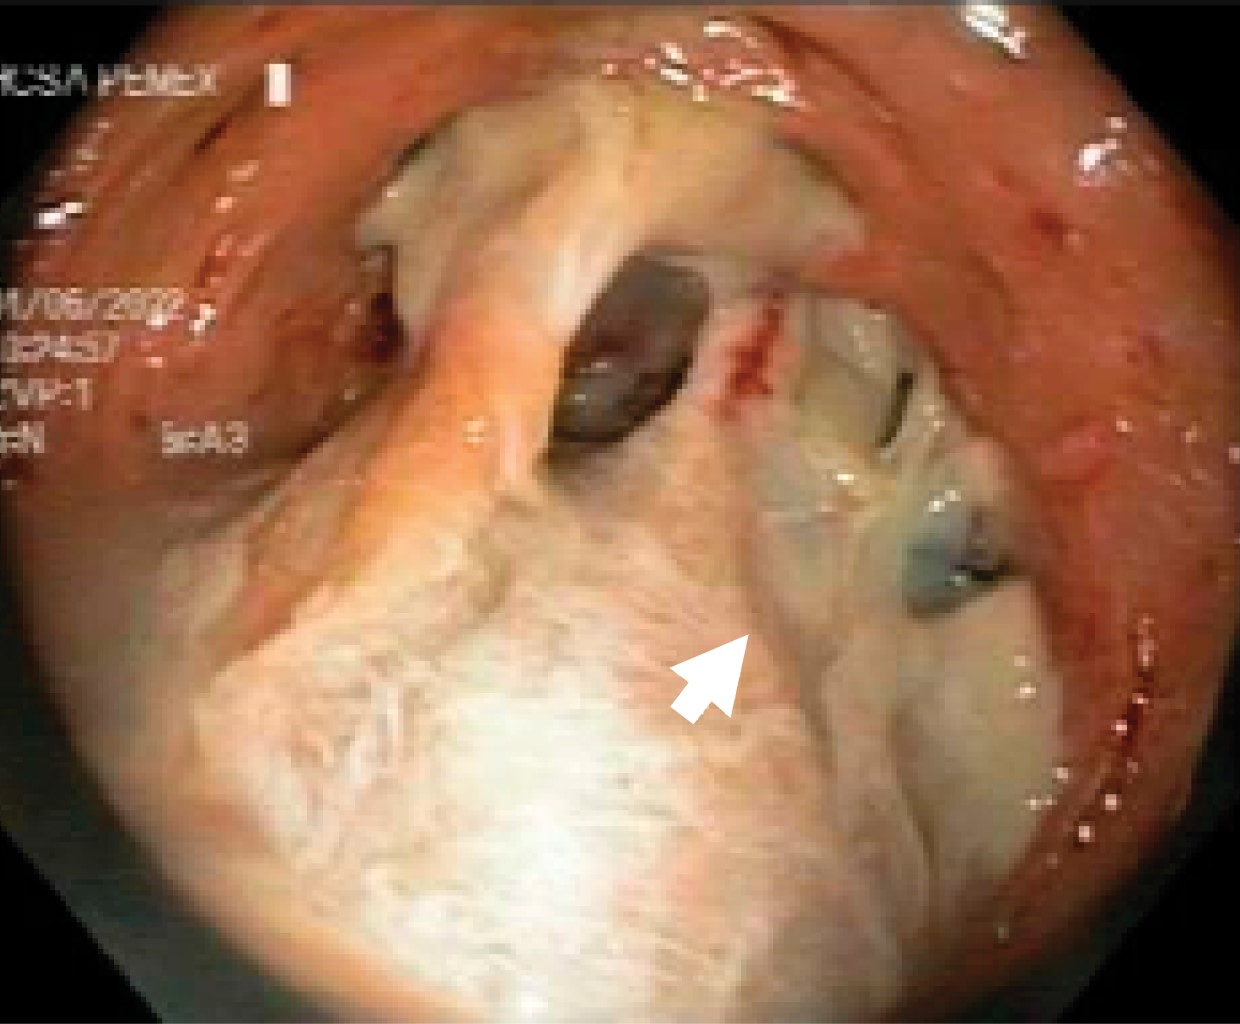

Figure 3